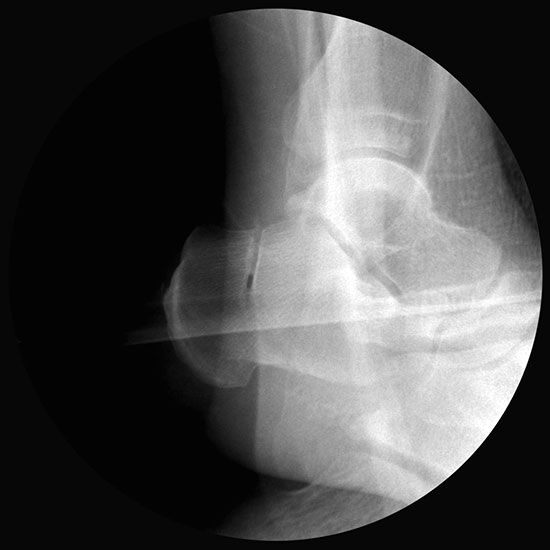

Bei Rückfussfehlstellungen ist meist eine knöcherne Korrektur des Kalkaneus indiziert. Dabei wird das Fersenbein im Bereich des Tuber calcanei durchtrennt und der Achillessehnenansatz nach medial oder lateral geschoben. Zusätzlich ist eine Rotation des Tuber möglich, wodurch sich der Korrektureffekt noch verstärkt. Durch die Wahl der Osteotomieebene kann die Verscheibung mit einer Verlängerung oder Verkürzung des Fersenbeins kombiniert werden. Die Osteosynthese erfolgt typischerweise durch perkutan eingebrachte Schrauben.

Bildwandler Bildgebung.

Bildverstärker.

Kanülierte Schrauben bis 80 mm Länge.

Kirschnerdraht mit 2,0 mm zur Verschiebung des Tuber calcanei.